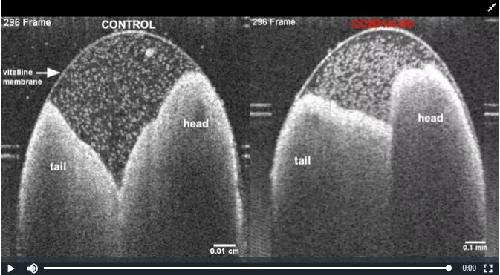

Analysis of Craniocardiac Malformations in Xenopus using Optical Coherence Tomography., Deniz E, Jonas S, Hooper M, N Griffin J, Choma MA, Khokha MK., Sci Rep. February 14, 2017; 7 42506. |

Xenopus Tadpole Craniocardiac Imaging Using Optical Coherence Tomography., Deniz E, Mis EK, Lane M, Khokha MK., Cold Spring Harb Protoc. June 7, 2022; 2022 (5): Pdb.prot105676. |

Quantitative Phenotyping of Xenopus Embryonic Heart Pathophysiology Using Hemoglobin Contrast Subtraction Angiography to Screen Human Cardiomyopathies., Deniz E, Jonas S, Khokha MK, Choma MA., Front Physiol. January 1, 2019; 10 1197. |